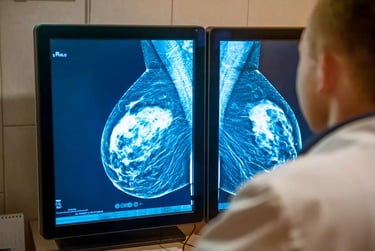

Mamografia

Exame radiológico das mamas, fundamental para a detecção precoce do câncer de mama, permitindo identificar alterações mesmo antes do surgimento de sintomas.